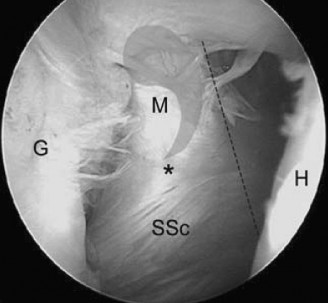

A standard posterior viewing portal is established. A thorough diagnostic arthroscopy of the glenohumeral joint is performed. The articular surface of the rotator cuff is inspected. An articular-sided partial tear (often referred to as a PASTA lesion - Partial Articular Supraspinatus Tendon Avulsion) will present as a detachment of the tendon from the medial footprint.

An anterior portal is established within the rotator interval. An arthroscopic probe is introduced to palpate the tear and assess the quality of the remaining tissue. The critical step is measuring the exposed footprint. A calibrated probe is used to measure the distance from the articular margin of the cartilage to the intact tendon insertion. If the exposed footprint measures greater than 7 mm, the tear is deemed >50% and warrants repair.

To correlate the articular findings with the bursal surface, a marker suture (e.g., PDS) is passed through the tear via a spinal needle from the subacromial space into the joint.